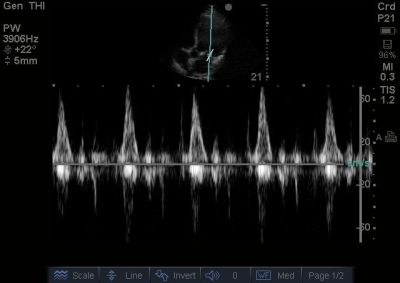

32yo M Mitral Doppler

[http://sonocloud.org/files/photos/1373605496135c3c_o.jpg]

This pulsed-wave Doppler image shows monophasic flow through the mitral valve with a nearly absent A-wave. This proves that in addition to systolic dysfunction, the patient has significant diastolic dysfunction as well in a restrictive pattern.